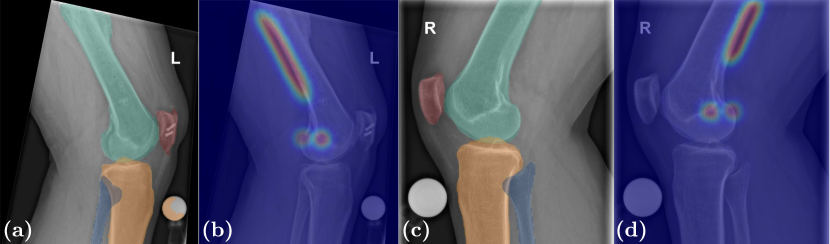

Refer to caption

Figure 3: Automatic results for multi-task segmentation (a,c) and localization (b,d). In (a), false-positive assignment of a spherical marker to the tibia is observed.

Predictions for the landmarks pblumsubscript𝑝blump_{\textrm{blum}} and ptmcsubscript𝑝tmcp_{\textrm{tmc}} are spatially precise with median Euclidean distance (ED) errors of 1.18,CI80%[0.99,1.74]mm1.18subscriptCIpercent800.991.74mm1.18,\allowbreak\,\textrm{CI}_{80\,\%}[0.99,1.74]\,\textrm{mm} and 2.14,CI80%[1.71,2.63]mm2.14subscriptCIpercent801.712.63mm2.14,\,\textrm{CI}_{80\,\%}[1.71,2.63]\,\textrm{mm} respectively (Fig. 3). In general, it can be observed that localization of ptmcsubscript𝑝tmcp_{\textrm{tmc}} is less robust due to its dependence on true-lateral imaging. Slight deviations from a true-lateral projection lead to non-overlapping femoral epicondyles, which necessitates three-dimensional reasoning and compensation for correct spatial positioning. For measuring the alignment of the cortical extension line, ED of the ground truth points pproxsubscript𝑝proxp_{\textrm{prox}} and pdistsubscript𝑝distp_{\textrm{dist}} to the predicted line are averaged, yielding a median score of 0.62,CI80%[0.48,0.79]mm0.62subscriptCIpercent800.480.79mm0.62,\,\textrm{CI}_{80\,\%}[0.48,0.79]\,\textrm{mm}.

The model consistently yields high overlap- and contour-based metric results and successfully delineates all target bone structures (Tab. 1). Qualitative assessment indicates successful disambiguation in overlapping areas, in narrow interarticular joint spaces, and in low-contrast regions (Fig. 3). Also, uncommon image characteristics like osteophytes along joint contours as well as aberrant lateral projections are resolved with high precision. However, subpar performance is observed for the fibula due to the proximal part being mostly overlapped by the tibia with seemingly no intensity shifts. Likewise, wrongful assignment of spherical markers to the tibia or the femur leads to high contour distances.